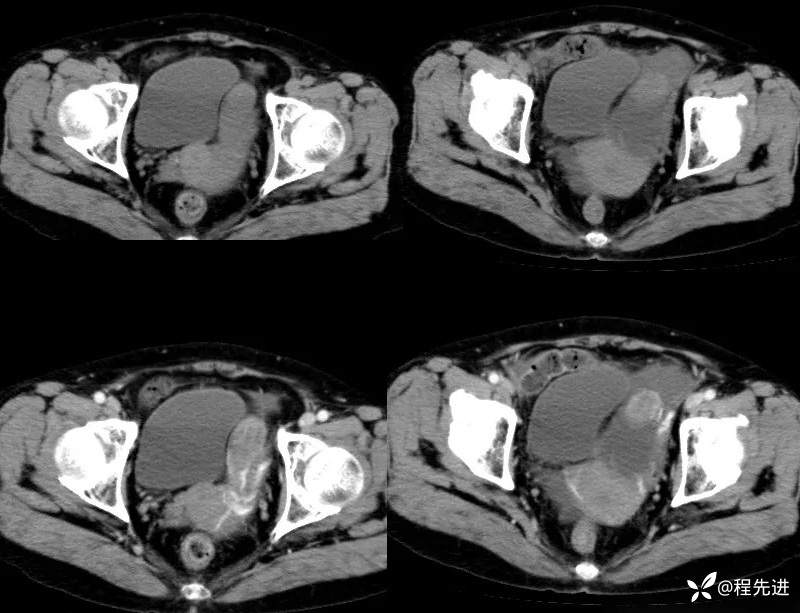

【患者信息】:女,59岁

【主诉】:下腹部不适2月,B超发现盆腔囊性包块。

实验室检查:CA125:239.1u/ml,CA72-4:99.64u/ml